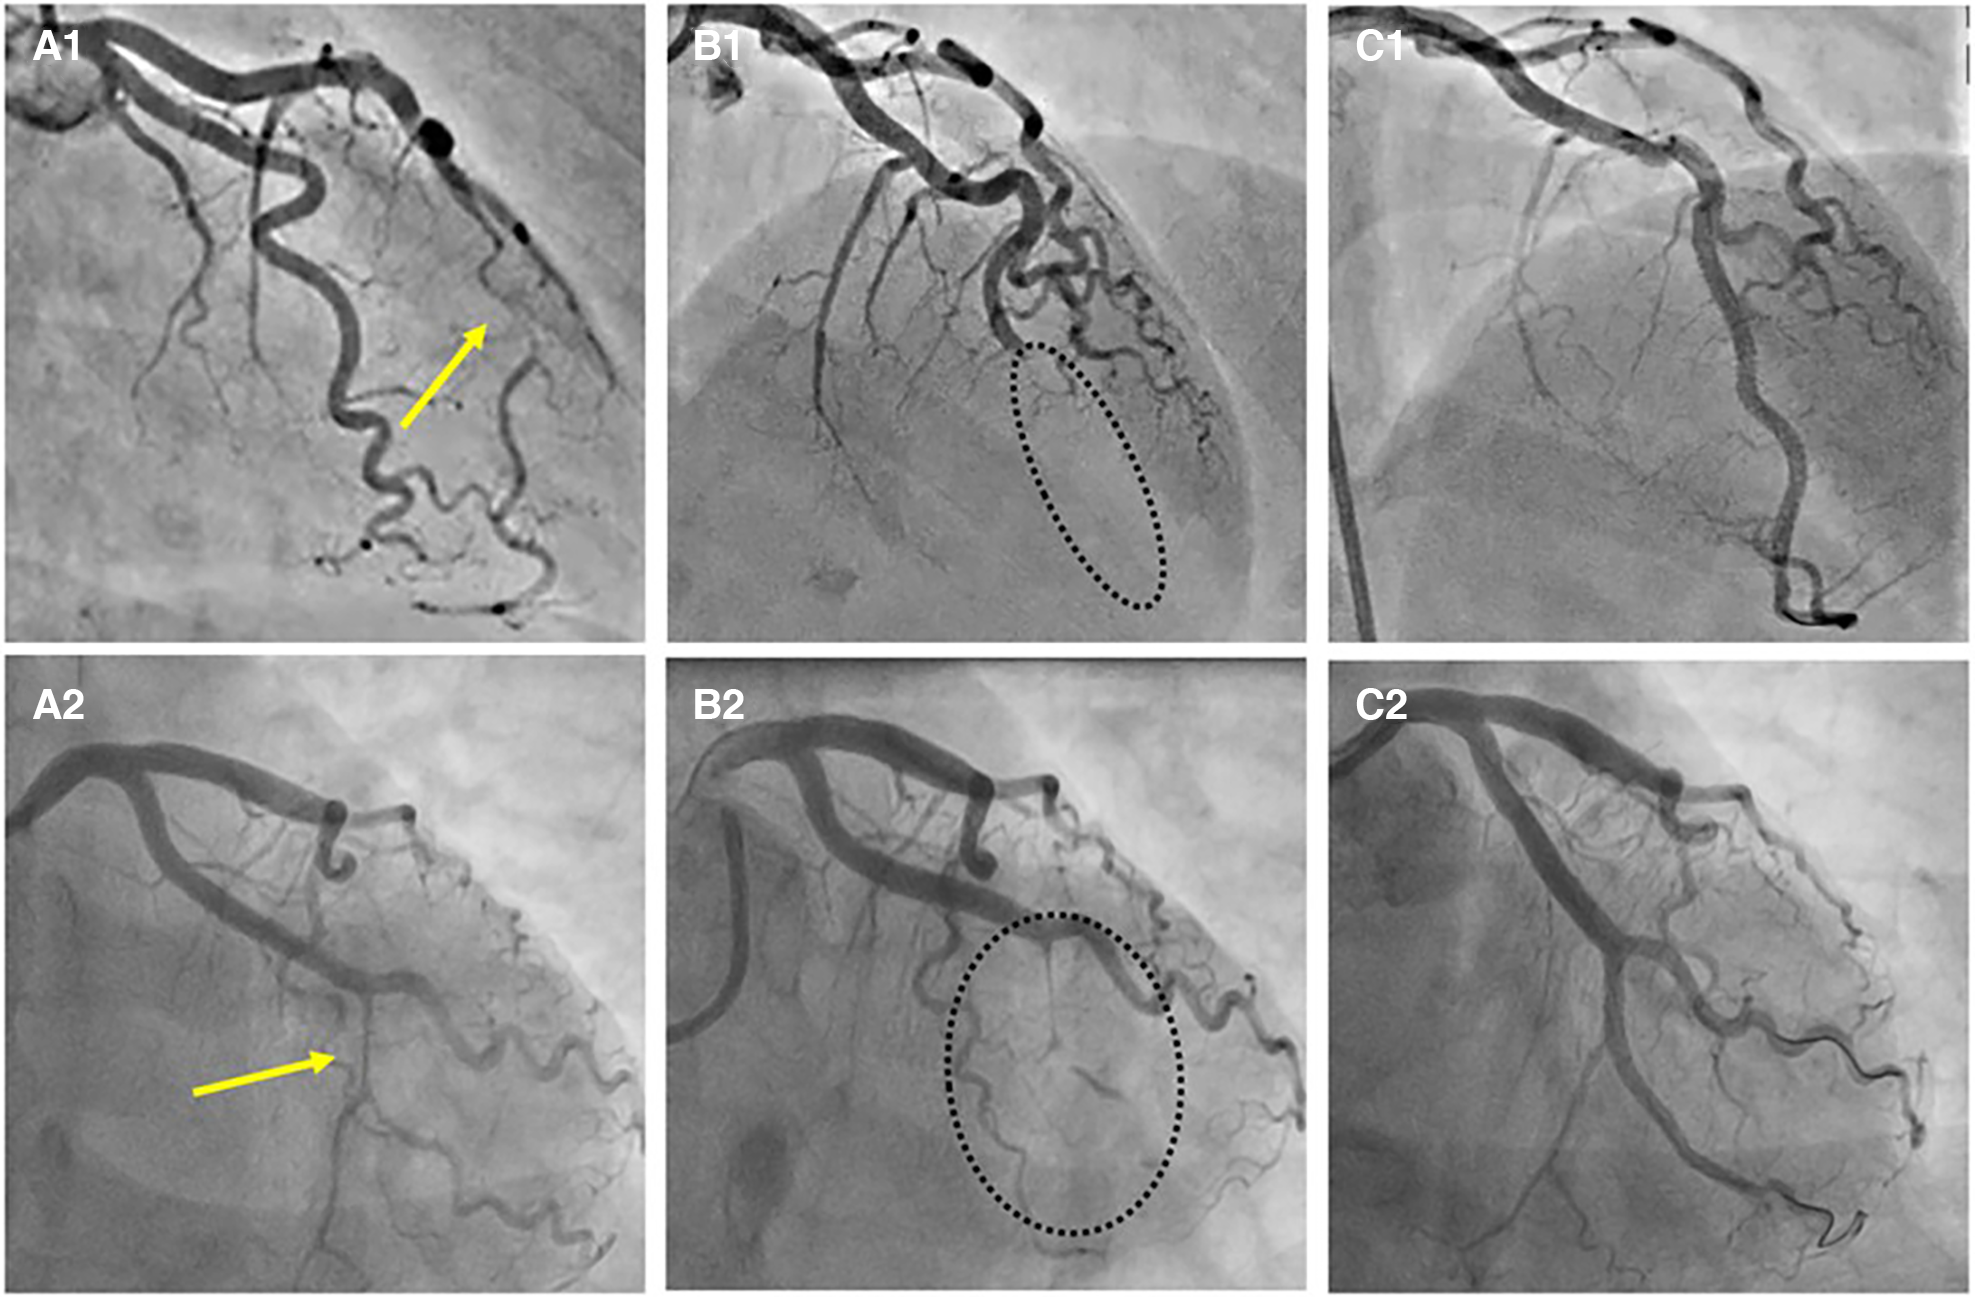

Type 1 angiographic appearance of SCAD is pathognomonic, usually developing in the late disease course, probably due to decompression of the false lumen hematoma into the true lumen. However, this angiographic finding has several mimickers, such as spontaneous recanalized coronary thrombus (SRCT) (56, 57) (Figures 3, panels B1, 2), atherosclerotic plaque rupture or erosion with apposition of thrombi (Figures 3, panels C1, 2), or even iatrogenic coronary dissection (Figures 3, panel D).

Figure 3

The angiographic differential diagnosis for type 1 SCAD. (A1) Type 1 SCAD with linear filling defect in mid-LAD. (A2) OCT finding in Type 1 SCAD- clear evidence of a small true (arrow) and a big false lumen with the OCT probe situated in the true lumen. (B1) Angiographic finding in spontaneous recanalized coronary thrombus (SRCT) in the mid and distal right coronary artery resembles SCAD. (B2) OCT finding in SRCT depicts a typical honeycomb-like structure. (C1) Angiographic finding in atherosclerotic acute coronary syndrome with plaque erosion and subsequent thrombus apposition. (C2) OCT finding corresponding to panel C1 with evidence of plaque erosion and intraluminal thrombi. (D) Angiographic finding in iatrogenic coronary dissection caused by guiding catheter, a picture resembling SCAD Type 1.

SRCT is a rare condition characterized by multiple communicating channels divided by thin septa, usually termed a “honeycomb-like” structure, “lotus root” appearance, or “Swiss cheese” pattern. The proposed mechanism of SRCT is the recanalization of an in-situ thrombus, formating several lumens which differ in size. To distinguish these two diagnoses, high-resolution intracoronary imaging techniques, intravascular ultrasound (IVUS) or optical coherence tomography (OCT), can be helpful (Figures 3, panels B1–2). Interestingly, “lotus root” pattern was recently observed in a patient with SCAD, possibly as a result of uncommon remodelling and healing pattern of subacute or chronic SCAD. (58)

Rupture or erosion of atherosclerotic plaque resulting in intraluminal thrombus formation can mimic type 1 SCAD as well (Figures 3, panels C1–2). Furthermore, contrast penetration into the atherosclerotic plaque core causing a localized plaque-associated dissection can resemble contrast penetration into the false lumen of a Type 1 SCAD. Although intraluminal thrombus might be seen in the occlusive (Type 4) SCAD, the presence of substantial thrombus and distal embolization should divert diagnosis to ACS caused by typical mechanisms, atherosclerotic plaque rupture or erosion. These two entities, although resembling angiographically, can be easily separated by intravascular imaging techniques (Figures 3 A1–2, C1–2).

Another feature similar in angiographic appearance to type 1 SCAD is iatrogenic coronary artery dissection (Figures 3, panel D). Furthermore, SCAD is associated with an increased risk for iatrogenic dissection (59), either due to the vulnerability of such coronary artery with predisposing arteriopathies, particularly FMD or due to the injury of thin intima with preexisting hematoma. Both deep guiding catheter intubation and the jet of contrast injection can make a tear into the vessel wall creating a typical picture of a dual (true and false) lumen. Other mimickers of SCAD type 1 include different contrast flow patterns simulating a linear filling defect, usually due to insufficient contrast volume or flow, and can easily be distinguished from SCAD by an experienced interventional cardiologist and by giving a more fulsome, generous contrast injection.

Recently described, Type 4 SCAD, characterized by a total occlusion of a distal vessel, is particularly ambiguous, usually misdiagnosed as atherosclerotic plaque rupture with thrombus formation as in STEMI and thus systematically treated with PCI. Coronary embolization from an upstream source of thrombi, such as prosthetic, mechanical valves or rheumatic valves, coronary aneurysms, or paradoxical embolization, can mimic Type 4 SCAD as well. Nevertheless, thorough anamnesis, inciting risk, and precipitating factors can raise suspicion of SCAD. Restoration of blood flow after wiring the artery can unmask typical SCAD features and, if combined with intracoronary imaging techniques, might enable definite SCAD diagnosis. If treated conservatively afterwards, complete vessel healing follows the natural SCAD process. Additionally, Type 4 frequently coexists with other types, either following Type 1, which can be the source of an embolus or continuing to other types, in which case IMH proximal to the occlusion can be detected by intravascular imaging techniques (Figure 8). SCAD progression from Type 1, 2 or 3 to Type 4 is also possible, particularly during a watchful waiting strategy in severe forms of SCAD (Figure 9).

Figure 9

Progression of SCAD. (A1) SCAD Type 2a in distal left anterior descending (LAD) artery (arrow), referred for OMT. (A2) SCAD Type 2a in left circumflex (LCX) artery (arrow), referred for OMT. (B1,B2) Progression to SCAD Type 4 during watchful waiting strategy-dotted lines depict missing LAD (B1) and missing LCX (B2). (C1, C2) Final result after PCI.